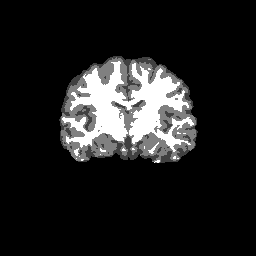

Accuracy is reported as Dice overlaps between a tool's segmentation and the Internet Brain Segmentation Repository (IBSR) manual segmentation for each of the 18 IBSR subjects. The inter-tool comparison (on the left below) shows the median Dice coefficient for each tissue class. The overlaps for FSL (from which the median values are drawn) are shown in the plot on the right.

Subject Accuracy (IBSR)

Overlap coefficients for each tissue class are shown here for each IBSR subject. Select a subject below to see the FSL results compared to other tools.